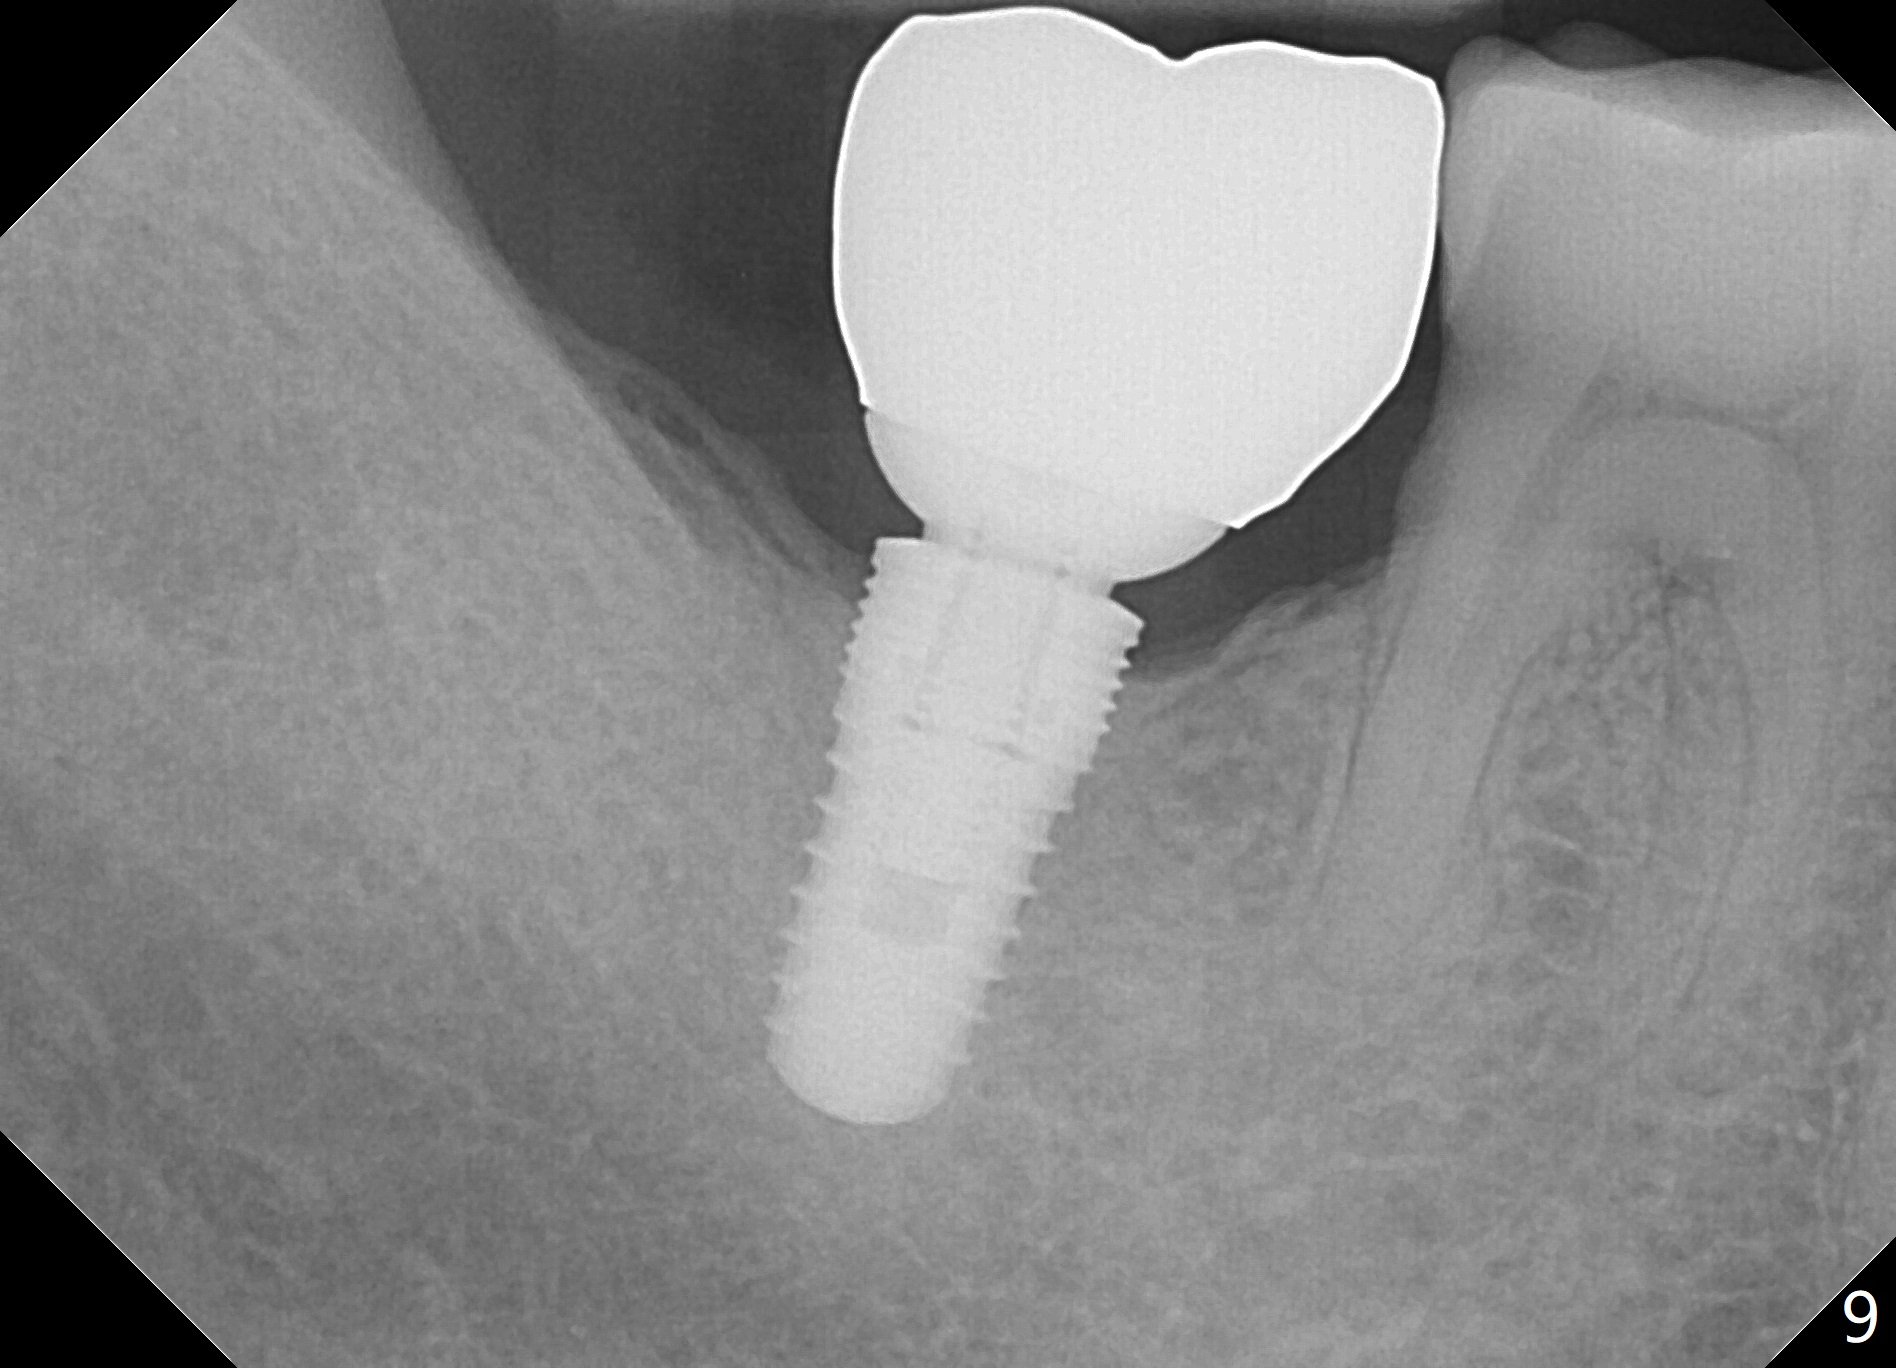

The bone feels to have relatively low density during osteotomy. The final osteotomy drill is 4.5x10 mm; a 5x10 mm implant is placed (under prep) with insertion torque >56 Ncm (Fig.6 I). A 6.8x4(2) mm cemented abutment (A) is placed immediately for an immediate provisional. The latter is opposed to the immediate provisional at #2.